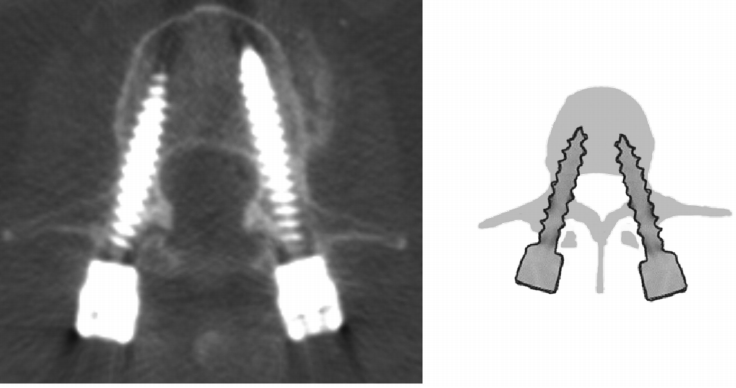

1.Herren分级

0级:螺钉没有触及小关节

1级:螺钉尾帽或连接部触及小关节

2级:螺钉穿透小关节的外侧下半部,但没有严重侵犯小关节内部

3级:螺钉完全位于小关节内部

4级:螺钉穿透椎弓根内侧边界,并穿透小关节上部